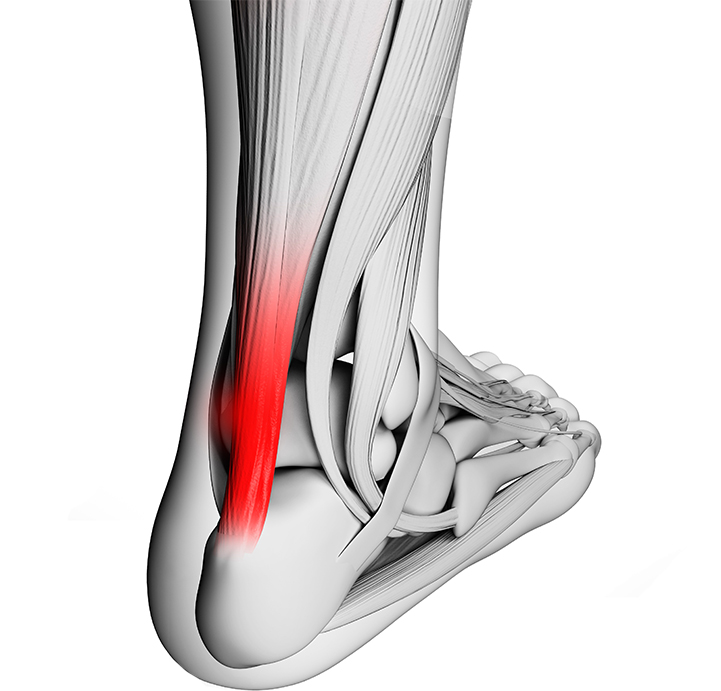

아킬레스건은 장딴지 근육과 발뒤꿈치 뼈를 연결하는 힘줄로 걷고 달릴 때 지렛대 역할을 합니다.

아킬레스건에 염증이 생겨 통증과 부종이 생기는 질환이 아킬레스건염 입니다.

증상을 방치할 경우 힘줄이 약화되고 파열로 이어질 수 있기 때문에 빠른 치료가 필요합니다.